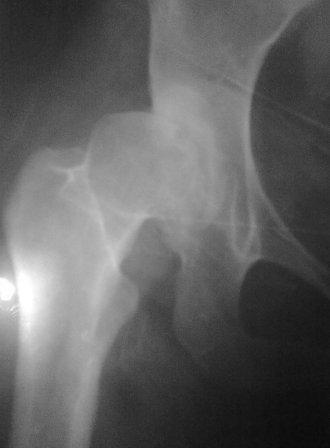

При определении показаний к м/в остеотомии учитываем не только функциональное состояние, но анатомическую форму сустава. Например, при той форме, что на картинке в вашем письме (мелкая впадина,уже не сферичная головка)НИИТО вполне обосновано предлагает ТЭП. Варизирующая остеотомия в "чистом виде" усилит конфликт в опорной зоне сустава. Если очень "настоятельно просит" - экстензия с наружной ротацией по R.Bombelli. То есть на открытом суставе бедро согнуть и ротировать внутрь до покрытия головки впадиной. Сформировать канал через шейку в головку с тем расчетом, что после м/в распила бедро нужно вывести в функциональное положение. Фиксировать 90 град. медиализирующей ортопедической пластиной с клинком. Но выздоровления не обещать, покрытие головки малое, длительного эффекта не будет. Нужна периацетабулярная остеотомия или пластика крыши, но это другая сложность и другая травматичность. Необходимость ТЭП оттянете лет на 10 в лучшем случае. Надо учитывать, что в этом случае ТЭП операция не первая, это увеличивает инфекц. риски и снижает функциональный результат для сустава. Я бы рекомендовал трость с противоположной стороны, ЛФК на приведение, чтобы подрос оссификат крыши и сформировались оссификаты головки. При нормотрофическом типе поражения можно будет провести вальгизирующую остеотомию, эффект которой более длительный или больная за это время найдет возможности приобретения ЭП.

Представляю Р-снимки: обзорная, с отведением и с приведением.

Глубокоуважаемый Абдурашид. Здесь нет снимка с отведением. Если Вы сами сходили в рентгенкабинет и лично отвели пораженную конечность максимально возможно, а также дали максимально возможную внутреннюю ротацию-это одно!!!! Значит у пациентки тяжелейшая приводящая контрактура тазобедренного сустава!! И необходимо разобраться-миогенная или артрогенная? Если же Вы просто назначили указанный снимок и доверили произвести укладку рентгентехнику-это другое!!! Одному богу известно, что она делала, ведь на р-снимке отведения нет!

Все предыдущие корреспонденты предлагают вам достаточно простую вещь-смоделировать предлагаемую Вами операцию (т.е. дать отведение и внутреннюю ротацию) и посмотреть, как изменятся соотношения в суставе. Не обижайтесь, но судя по представлению клинического случая угловые величины, характеризующие пространственные соотношения в тазобедренном суставе, ваши рентгенологи не считают.

Уважаемый Игорь Владимирович. диссертации М М Камоска, и В Е Баскова я нашел, но почему-то не могу открывать, и еще в данном случае имеется дисплазия т/б за счет недоразвития крыши в/впадины да и всей подвздошной кости, маргинального вывиха или латеропозиции головки вследствие лечебных ощибок нет, головка стоит на месте. Р-граммы сделал сам, но почему-то у больной отведение и внутренная ротация стали очень болезненной, и сухожилия приводящих мышц сильно натягивается.(контрактура артро-миогенная).

Глубокоуважаемый Игорь Владимирович! Признаюсь допустил ошибку, из-за напряженности работы и нехватки времени, когда повторно внимательно посмотрел все понял и не успел исправить ошибку до Вашего поста, конечно скошенность крыши в пределах 40гр,часть головки кнаружи линии Омбредана-Перкинса , облитерация дна вертлужной впадины и т.д.-это ДМВБ.